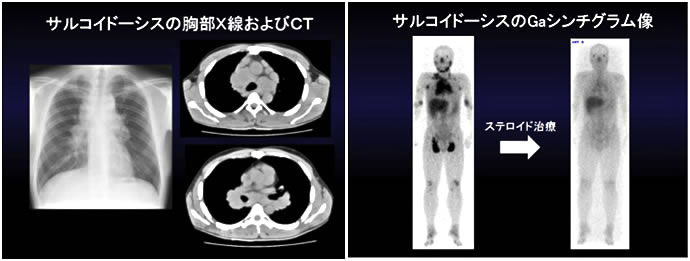

図13. サルコイドーシスの典型的な画像(自験例)

両側肺門リンパ節の腫大を胸部X線写真および胸部CTで認め、Gaシンチグラムでの取り込み(黒く染まっている部分)はステロイド治療により減少することが分かります。